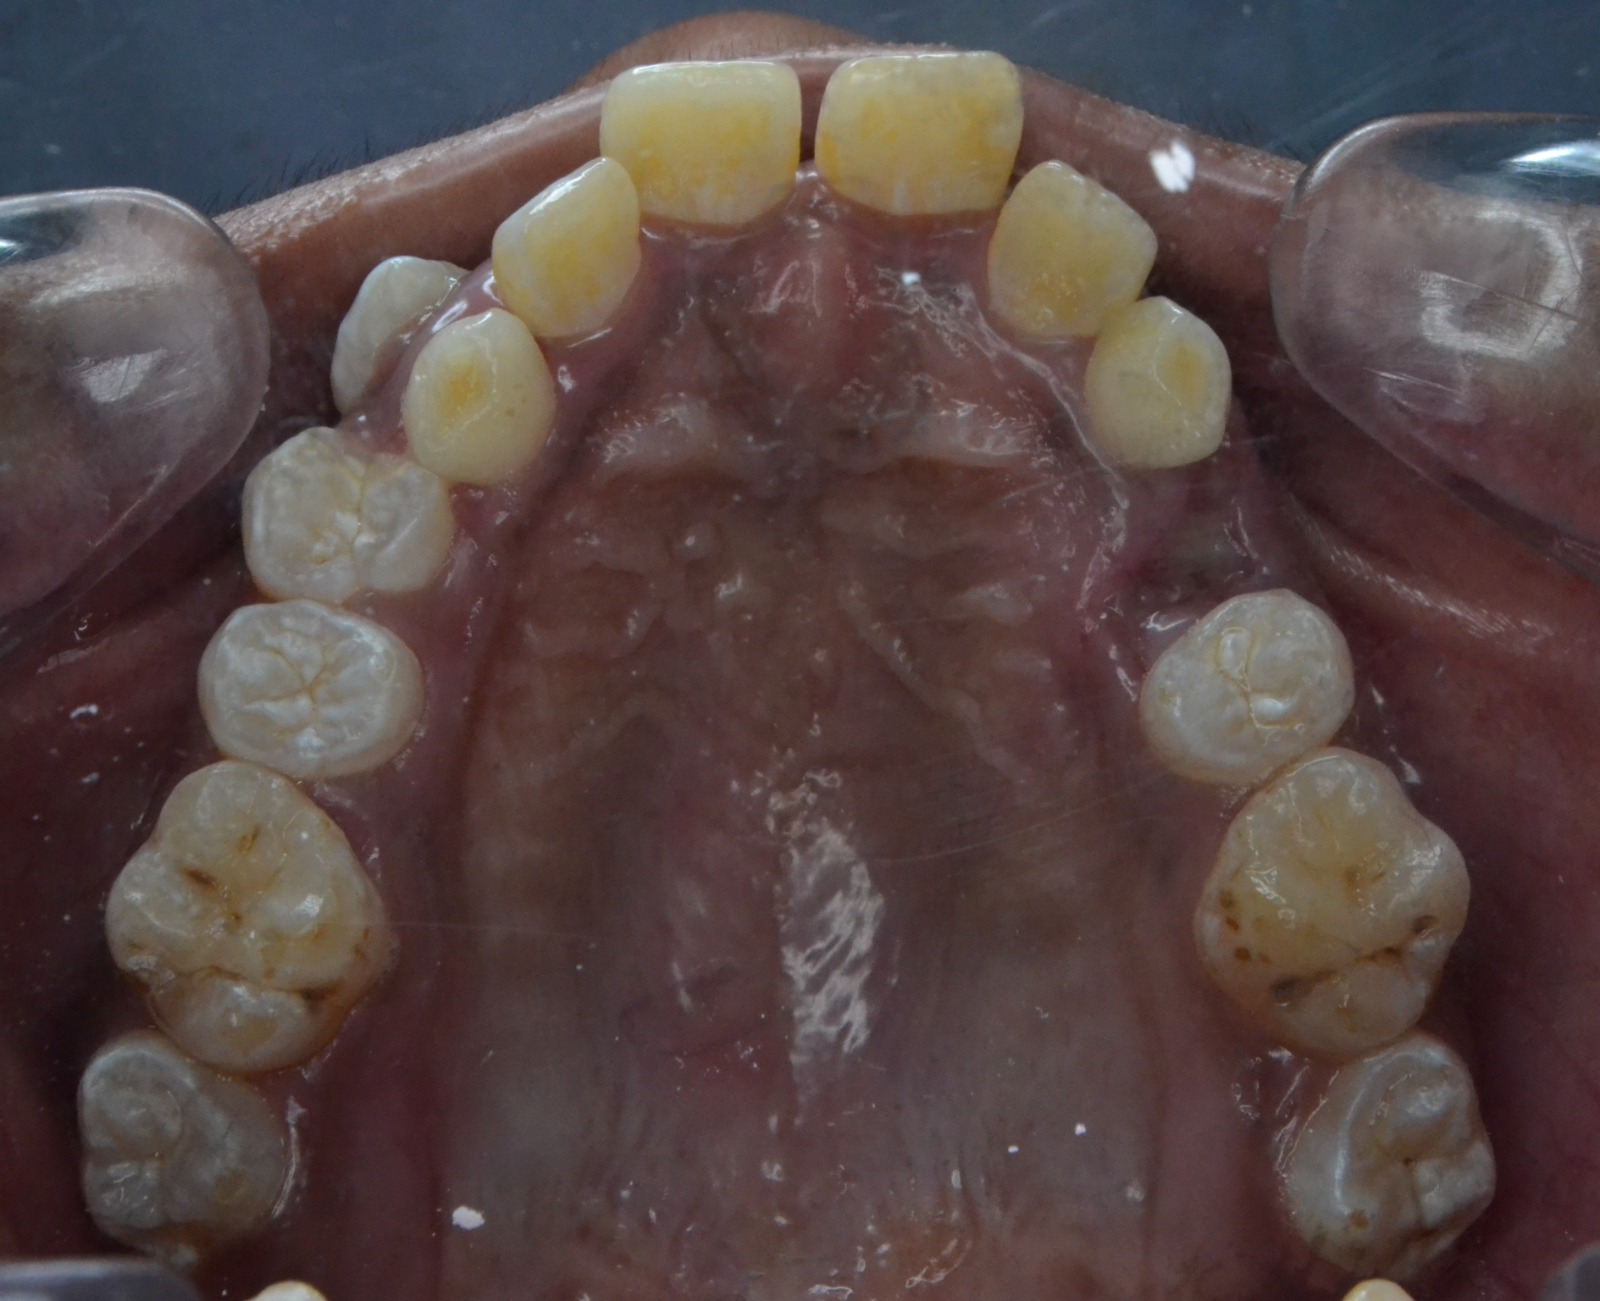

Sairam dental care located in Dharmapuri, with Leading Dentist In Oddapatti, is the Dental Hospital with exclusive root canal, Braces & Invisalign center. Led by renowned Drs Raghuraaman ( Periodontist) and Nivetha Raghuraaman ( Orthodontist) Sairam dental care offers gum treatment with expertise in laser, root canal treatment and digital smile correction with advanced technology aim to focus on aesthetics, comfort and precision. The clinic also specializes in Invisalign treatment, digital smile makeover, laser gum care, dental implants, root canal therapy, extractions and full-mouth rehabilitation blending compassionate care and clinical excellence.